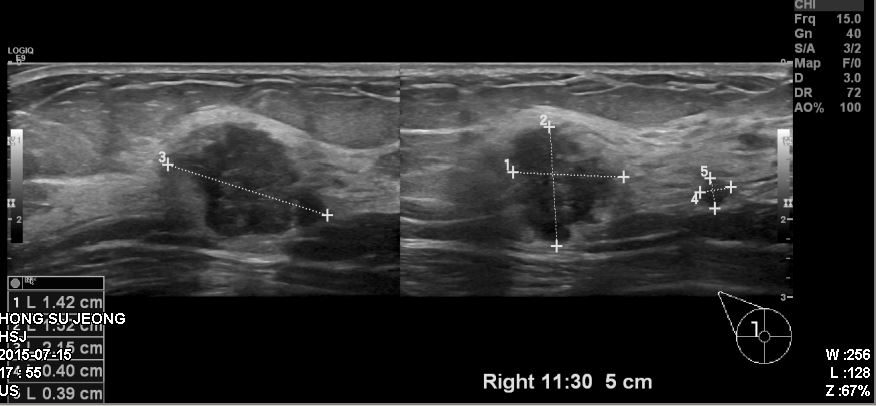

우측유방에 만져지는 혹으로 내원하신 40대 환자분이십니다.

본원에서 우측 11:30 방향에 확인되는혹 조직검사 시행하였고

결과상 침윤성유관암 진단되었습니다